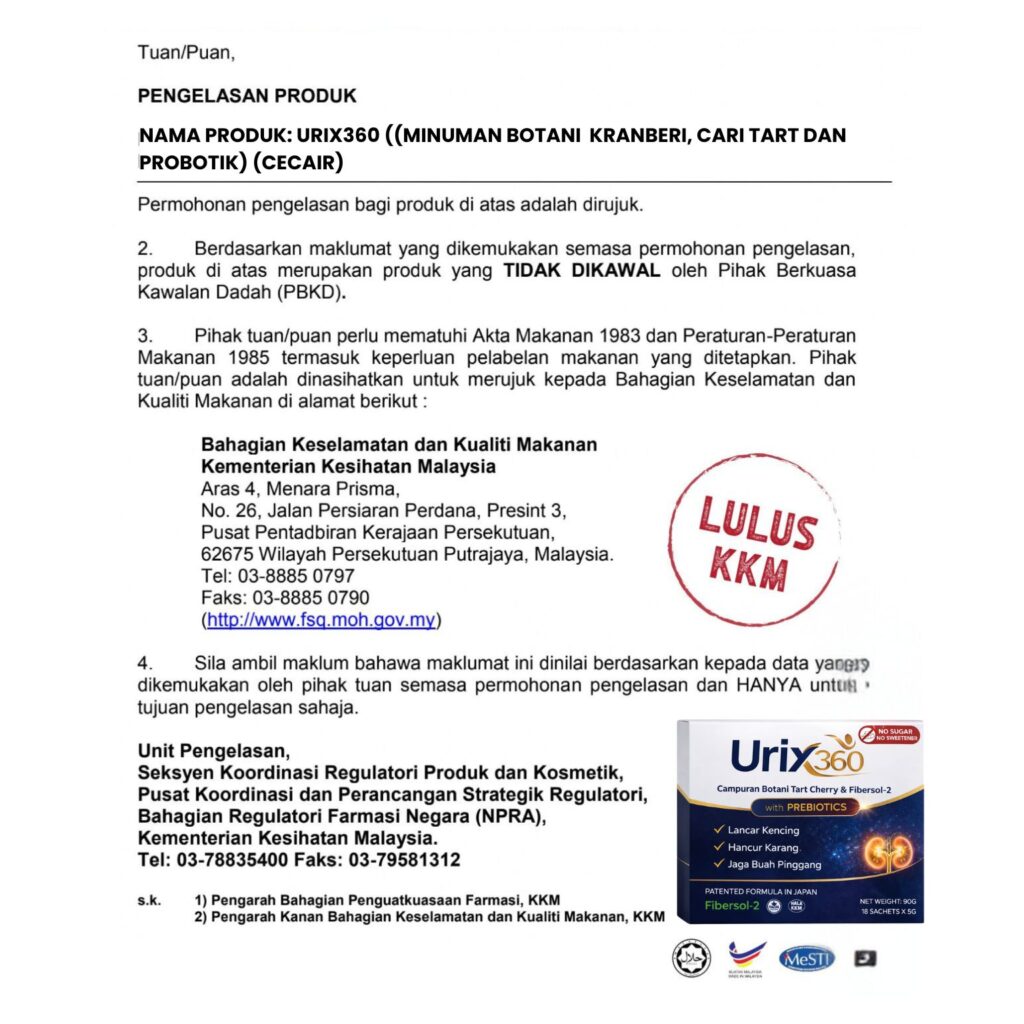

Jangan Risau Urix360™

Selamat Digunakan

Boleh Amalkan Tanpa Was-Was

Urix360 100% Selamat, Halal dan Telah Menjalani Ujian Makmal Yang Diluluskan Oleh KKM

Tiada kesan sampingan oleh kerana URIX360 adalah minuman botanik yang berasaskan daripada tumbuhan/buah-buahan terpilih di mana 100% berasaskan bahan semulajadi Ada kelulusan KKM & Ujian Klinkal Dan LabTES

Tidak. URIX360 ini adalaah minuman botani yang telah melepasi ujian labtest di mana 100% bahan digunakan 100% selamat tanpa kesan sampingan.